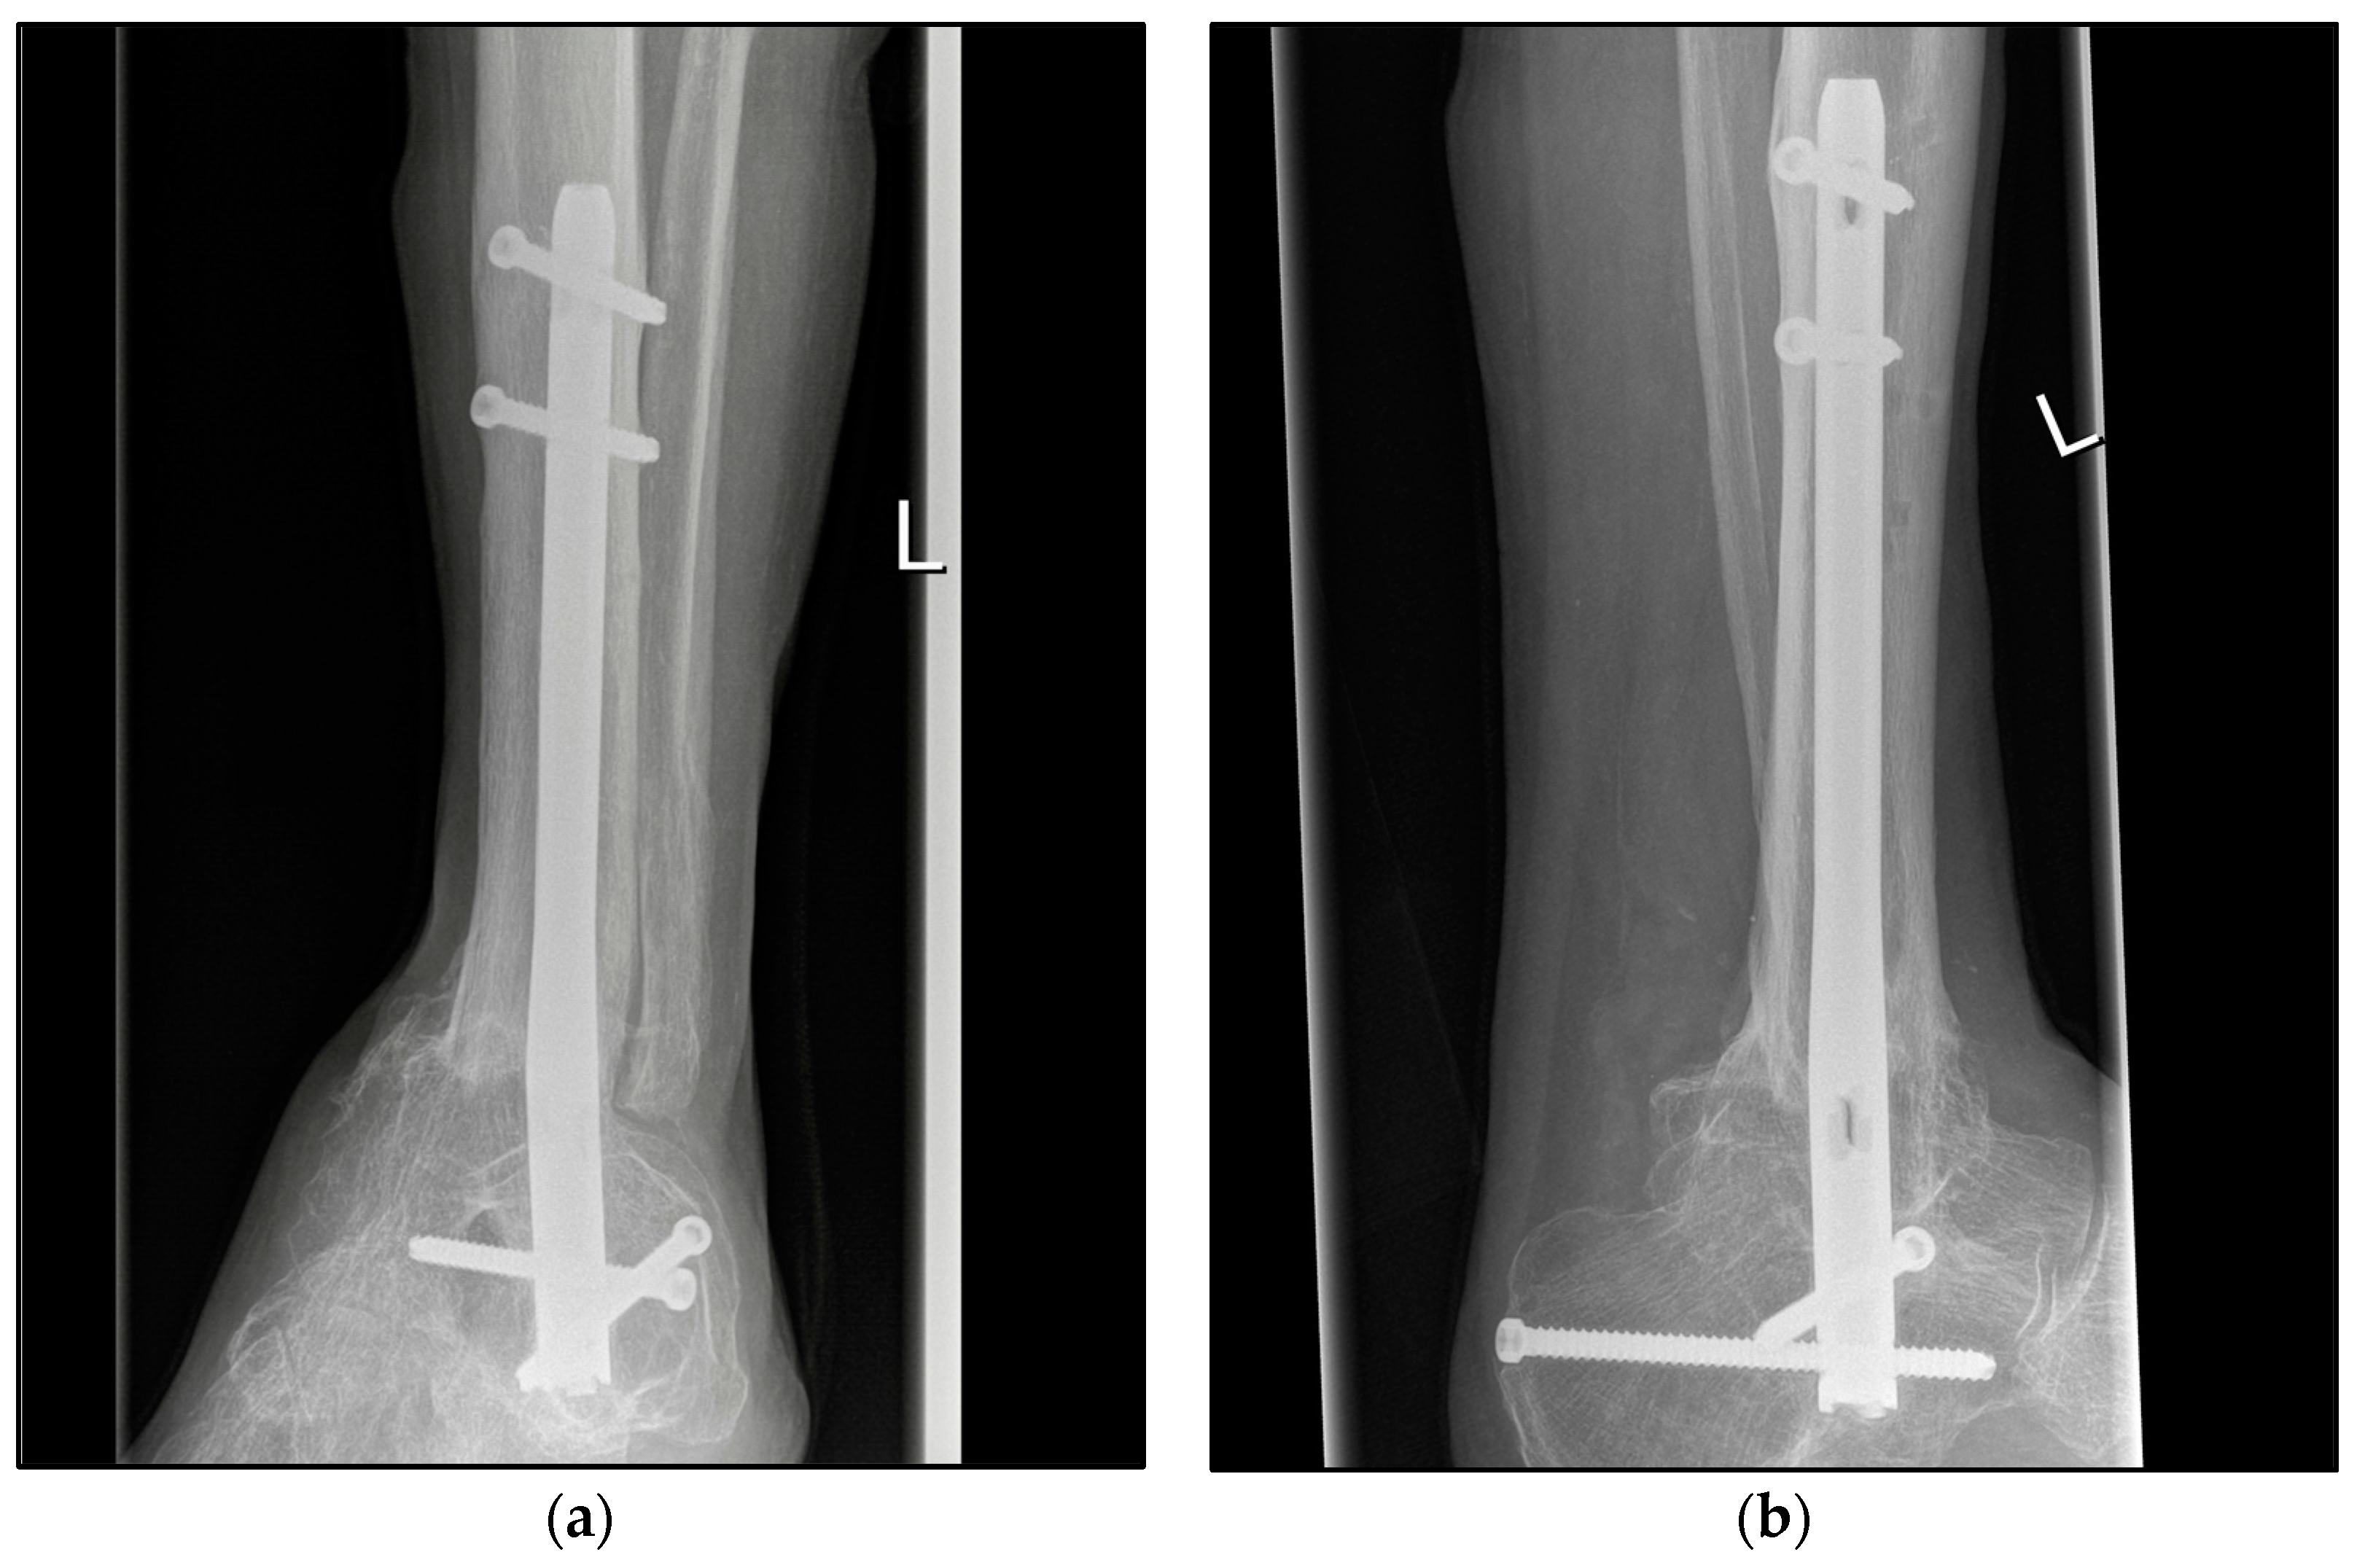

Figure 2.

Postoperative radiographic findings of end-stage posttraumatic arthritis of the left ankle with septic history of a 54-year-old male treated with a screw fixation due to nonunion after tibiotalocalcaneal arthrodesis treated with arthrodesis nail. (a,b) Anteroposterior and lateral view; view, 6 years post operation.